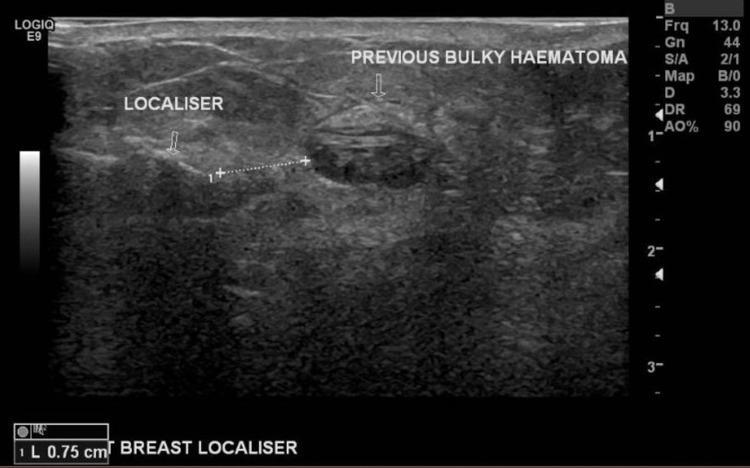

Breast augmentation has been gaining popularity over the last two decades to correct congenital breast asymmetry or increase breast size and projection. Augmentation options started with saline implants, then silicone implants, and, recently, autologous fat transfer. Unfortunately, breast implants are not without complications, some of which are common, like capsular contracture, implant failure and infection. Others are quite rare, such as Breast Implant-Associated Anaplastic Large Cell Lymphoma (BIA-ALCL). Most of these complications will eventually require explantation in most cases, as the patients' and implants' age and risk of complications increase. We present a 79-year-old patient who presented to our breast unit with a left breast lump with 50-year-old saline implants. A triple assessment revealed incidental right breast cancer treated with radiofrequency identification (RFID) tag-guided wide local excision, sentinel lymph node biopsy and bilateral explantation.

在过去二十年中,隆胸手术越来越受欢迎,用于矫正先天性乳房不对称或增加乳房大小和凸度。隆胸的选择最初是盐水植入物,然后是硅胶植入物,最近则是自体脂肪移植。不幸的是,乳房植入物并非没有并发症,其中一些很常见,如包膜挛缩、植入物失效和感染。其他则相当罕见,如乳房植入物相关间变性大细胞淋巴瘤(BIA-ALCL)。在大多数情况下,随着患者和植入物的年龄以及并发症风险增加,这些并发症中的大多数最终都需要取出植入物。我们介绍了一位79岁的患者,她因左乳房肿块来到我们的乳腺科,其乳房中植入了已有50年历史的盐水植入物。三重评估发现了偶然的右乳癌,通过射频识别(RFID)标签引导的广泛局部切除、前哨淋巴结活检和双侧植入物取出进行了治疗。